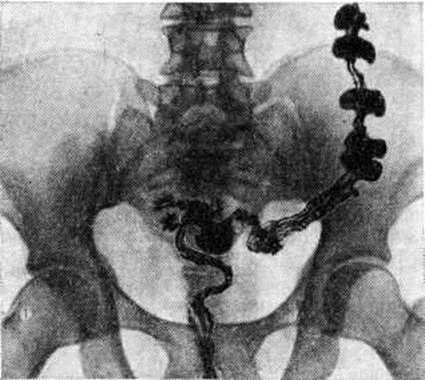

Рис 2.

Рентгенограмма толстой кишки при гиперкинетическом запоре (колит) через 72 часа после приёма бария внутрь: тонус нисходящей и сигмовидной кишок резко повышен, отдельные участки кишки спастически сокращены (участки спастически сокращённой кишки, не заполненные контрастной массой, обозначены белой пунктирной линией).

При первичных Запоры обычно обнаруживают снижение моторной функции, повышение, или понижение тонуса кишки. Эти изменения могут распространяться на всю кишку или на отдельные её сегменты (рисунок 1). Рельеф слизистой оболочки имеет нормальный или несколько «раздражённый» характер (ирритационный рельеф): складки приподняты, расположены более продольно или поперечно, но лишены, признаков воспаления. Смещаемость кишки не нарушена. При гиперкинетических Запоры замедление пассажа бария сочетается с регионарным спазмом и глубокой, нередко сегментирующей гаустрацией в виде многочисленных перетяжек (рисунок 2). Спазмированный отдел кишки иногда имеет вид тонкого шнура (рисунок 3). Реже, при атонических Запоры, обнаруживают пониженный тонус всей толстой кишки или отдельных её сегментов, сопровождающийся расширением просвета, поверхностной сглаженной гаустрацией.